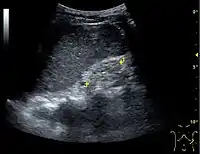

Kidney ultrasonography is useful for diagnostic and prognostic purposes in chronic kidney disease. Whether the underlying pathologic change is glomerular sclerosis, tubular atrophy, interstitial fibrosis, or inflammation, the result is often increased echogenicity of the cortex. The echogenicity of the kidney should be related to the echogenicity of either the liver or the spleen (Figure 22 and Figure 23). Moreover, decreased kidney size and cortical thinning are also often seen and especially when disease progresses (Figure 24 and Figure 25). However, kidney size correlates to height, and short persons tend to have small kidneys; thus, kidney size as the only parameter is not reliable.[54]

Chronic renal disease caused by glomerulonephritis with increased echogenicity and reduced cortical thickness. Measurement of kidney length on the US image is illustrated by '+' and a dashed line.[54]